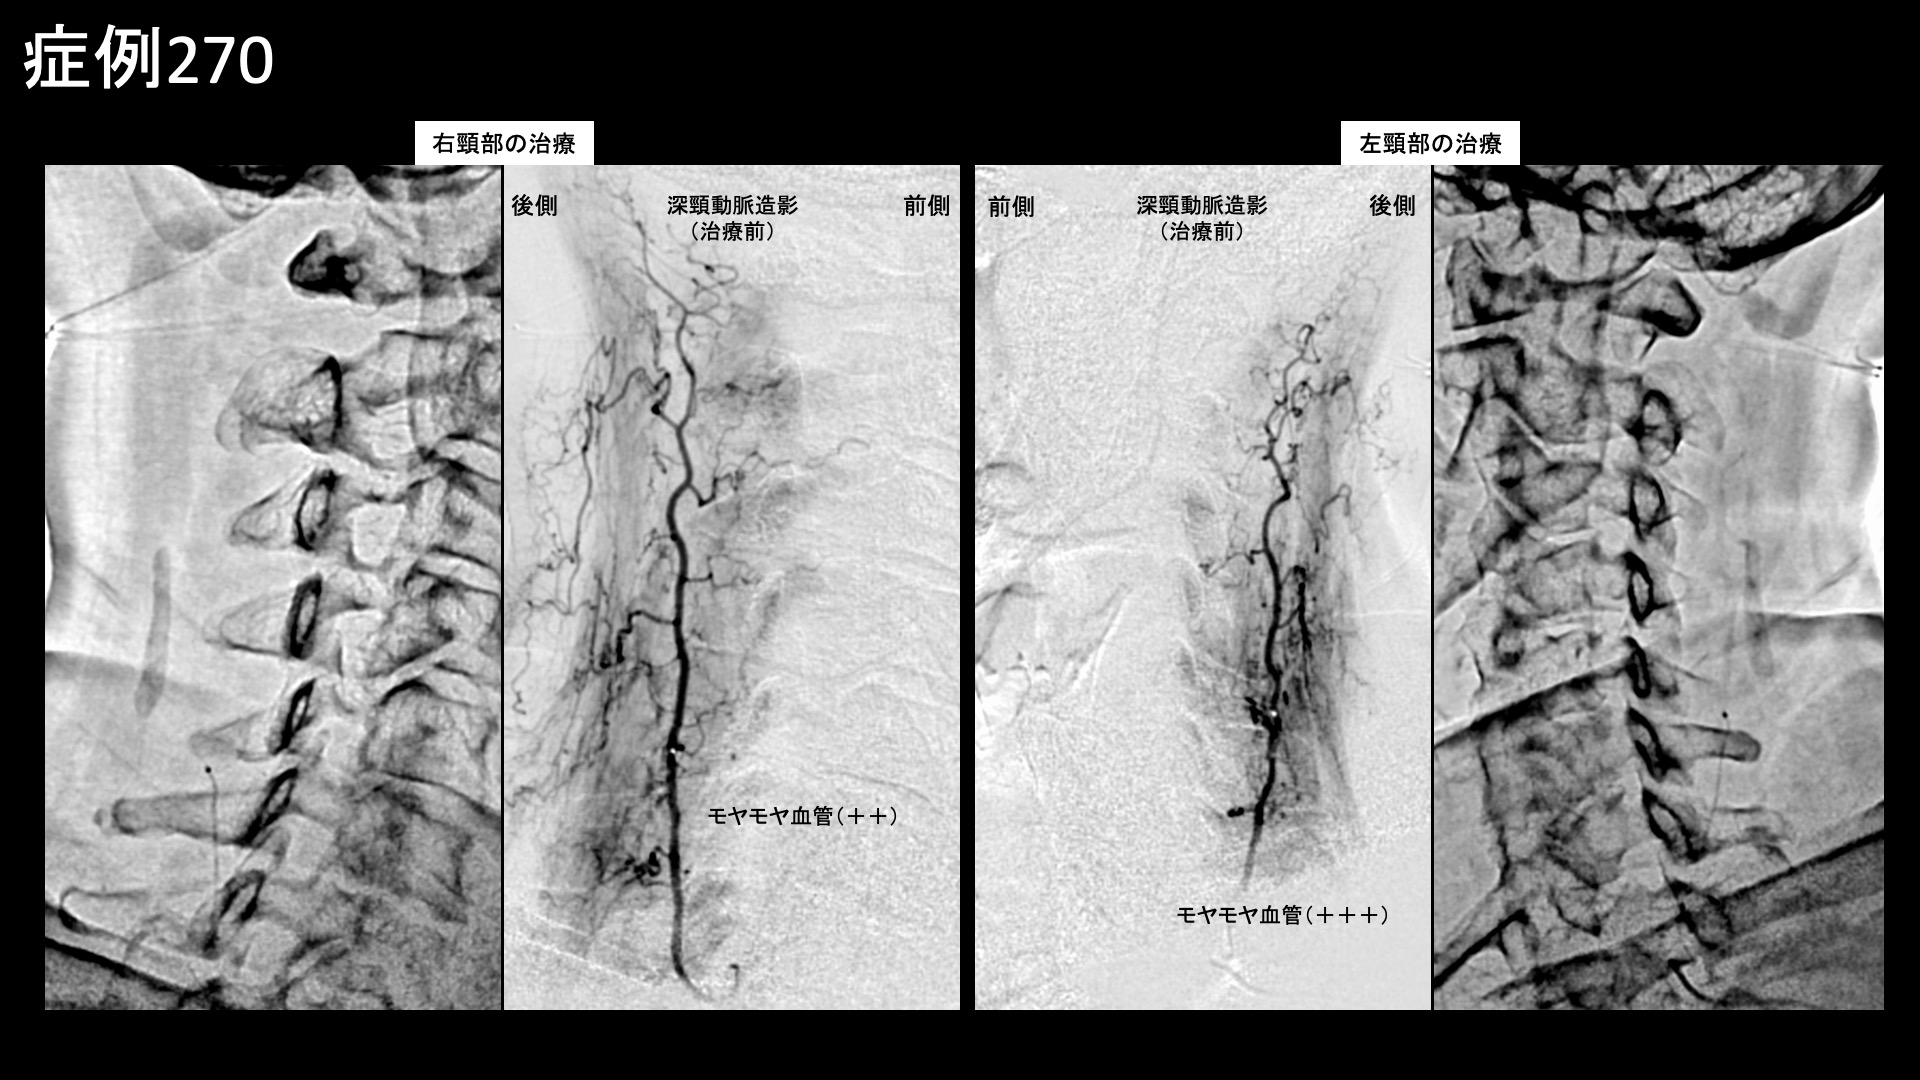

肩:肩こり・四十肩・五十肩 【50代:女性】両腕が使えず夜も眠れず、生活を一変させたまさかの両側五十肩に対するモヤモヤ血管治療(五十肩、凍結肩、肩関節周囲炎) 2026.03.13 鴨井院長による動画解説 受診までの経過 11ヶ月前から左肩が痛むようになり、整形外科や鍼灸院など複数の施設に通いました。3ヶ月くらいで治ると言われ、注射治療などを受けましたが、半年くらいでようやく少しおさまったものの腕はいっこうに上がりませんでした。それどころか右肩も痛くなり、夜間痛や起床時痛にも見舞われ、朝から気力を奪われてしまい、洗髪・洗顔など日常生活にも大きく支障をきたすようになりました。元々は毎日出かけたい性分でしたが、最近はどこにも行きたくなくなってしまうほどでした。 診察時の所見 両肩とも同程度の可動域制限を認め、外転45度、外旋5度、反対の肩に手を回すことはできず、後ろに手を回すのは臀部を触るのがやっとでした。首肩こりもあり、触診上は中等度以上でした。レントゲンでは肩関節や頸椎は概ね保たれていましたが、後頸部に項靭帯石灰沈着を認め、頸部への負担が蓄積してきたことは明らかでした。エコー検査では腱板などは保たれている一方で腱板粗部や上腕二頭筋長頭腱周囲に異常血流信号を認めました。僧帽筋および周囲組織の線維化所見も認められました。肩関節は、器質的異常がない一方で強い炎症が存在する、典型的な凍結肩(五十肩)の所見でした。治療対象となる程度の、一定以上の首肩こり所見も認められたため併せてモヤモヤ血管(病的新生血管)に対する運動器カテーテル治療(微細動脈塞栓術)を受けていただきました。 治療の所見 血管造影を行うと、首こりの主要責任血管である深頸動脈にてモヤモヤ血管が濃染像として描出されました。肩こりの治療も行った後、肩関節の血管造影を行うと、肩甲上動脈、胸肩峰動脈、烏口枝、前上腕動脈の各血管で同様にモヤモヤ血管を認めました。治療後は画像上速やかに消失しました。その他複数箇所の治療を行い終了しました。 治療前画像:損傷を受ける、あるいは繰り返しのストレスにより発生した異常な新生血管 治療後画像:カテーテルを用いて塞栓物質を血管内に投与し新生血管を塞いだ状態 治療費用:治療する部位によって費用が異なりますのでこちらをご参照ください。 主なリスク・副作用等:針を刺した場所が出血により腫れや痛みを生じたり、感染したりすることがあります(穿刺部合併症)。造影剤によるアレルギー(皮膚のかゆみ・赤み・息苦しくなるなどの症状)が出ることがあります。 治療後の経過 治療翌日から改善し、よく眠れるようになりました。朝のこわばりも無くなりました。治療後2週間の再診時にはとても明るい表情をされていました。治療後1ヶ月半、痛みは消失していました。可動域も外転100度と大幅に改善していました。治療後2ヶ月半で外転160度まで改善しました。まだバンザイまではできないものの、日常生活で困ることは無くなりました。非常に経過良好であり、自然経過による完治が見込まれたため終診としました。腱板断裂などの器質的異常がありませんので、完全に治ります。 両側とも五十肩に罹患した症例でした。様々な報告がありますが、両側に罹患するのは10-20%、同時に罹患するのは数%程度と言われています。両肩とも外転45度程度までしか動かせず、夜間痛で眠れない日々が続くと、どんなに前向きな性格の方でも心まで病んでしまいます。改善後の明るい表情がとても印象的でした。凍結肩はカテーテル治療の良い適応疾患の一つであり、有効性は極めて高いです。お困りの方はお気軽に御相談ください。 五十肩の詳細はこちら 【10代:女性】水泳の国体選手が決断した外踝(くるぶし)の痛み(腓骨筋腱炎)に対するモヤモヤ血管治療(腓骨筋腱炎、外踝の痛み) 前の記事 【10代:男性】サッカーをすると膝の下が痛む~小学生のオスグッド病に対するモヤモヤ血管治療~(オスグッド病) 次の記事